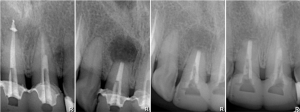

В настоящий момент производители выпускают линейки имплантов, предназначенных для установки в лунку только что удаленного зуба. Они отличаются крупной агрессивной резьбой, назначение которой – обеспечить качественную стабилизацию импланта в условиях лунки только что удаленного зуба.